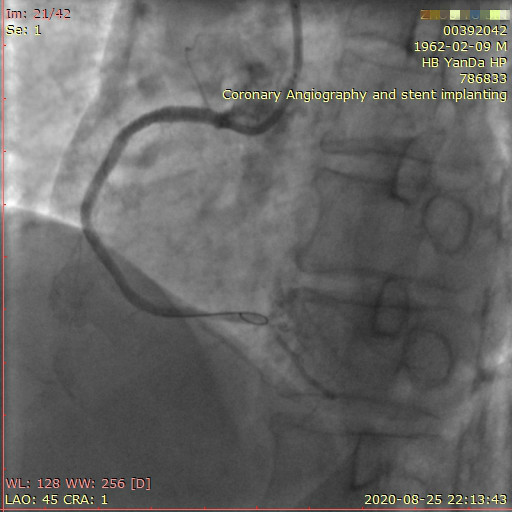

李先生蜘蛛位術(shù)前影像

李先生蜘蛛位術(shù)后影像

術(shù)前,翟光耀主任還親自為李先生復(fù)查冠狀動(dòng)脈造影,造影結(jié)果顯示:患者的前降支、回旋支、右冠等冠脈三支嚴(yán)重病變、嚴(yán)重鈣化,且均為彌漫性長(zhǎng)病變,最重處99%以上管腔極嚴(yán)重狹窄。翟主任仔細(xì)閱讀造影結(jié)果后指出:結(jié)合李先生的實(shí)際情況,雖然微創(chuàng)介入手術(shù)難度比較大,但仍可行;李先生心臟三支主干動(dòng)脈均存在極其嚴(yán)重的狹窄,每一支動(dòng)脈均至少植入2-3枚支架,根據(jù)患者的耐受情況,李先生可能需要分3次分別對(duì)三支動(dòng)脈進(jìn)行介入手術(shù);考慮到李先生路途遙遠(yuǎn),病情嚴(yán)重,不宜反復(fù)奔波,并且患者迫切要求能夠徹 底解決病痛,在病情允許的情況下,如果手術(shù)順利,爭(zhēng)取為患者進(jìn)行“一站式”手術(shù),一 次 性解決全部三支動(dòng)脈病變!

手術(shù)方案確定之后,在心血管內(nèi)三科趙景新主任、介入醫(yī)學(xué)科富孝晨主任的配合下,翟光耀主任親自擔(dān)任主刀,分別依次對(duì)李先生的三支動(dòng)脈進(jìn)行了完全血運(yùn)重建。由于手術(shù)進(jìn)展順利,李先生術(shù)中沒(méi)有任何癥狀,耐受良好,于是成功的將三支動(dòng)脈“一站式”治療!術(shù)中,由于李先生左主干遠(yuǎn)端分叉處存在嚴(yán)重病變,翟光耀主任選擇國(guó)際指南推薦的DK-mini-Crush技術(shù),確保了分叉處兩支主干開(kāi)口均萬(wàn)無(wú)一失。據(jù)悉,DK-mini-Crush技術(shù)是目前冠脈分叉病變領(lǐng)域最為復(fù)雜及難以掌握的介入技術(shù)之一,對(duì)手術(shù)醫(yī)生經(jīng)驗(yàn)、體力均提出了極大的挑戰(zhàn)。極為擅長(zhǎng)復(fù)雜介入技術(shù)的翟光耀主任卻用嫻熟的技術(shù)確保了李先生手術(shù)的成功。